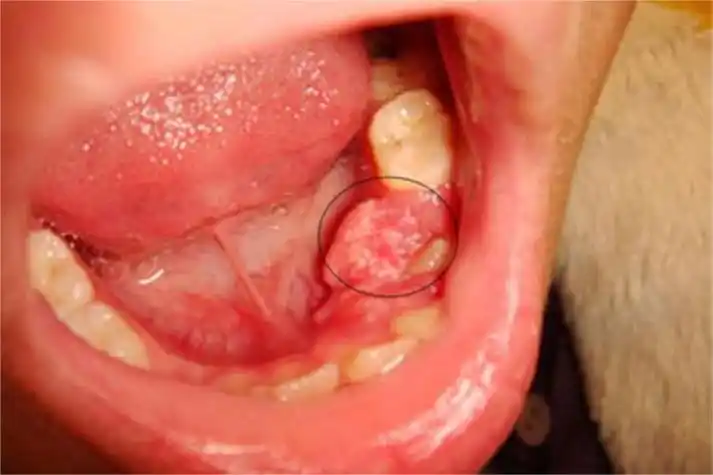

牙龈癌图